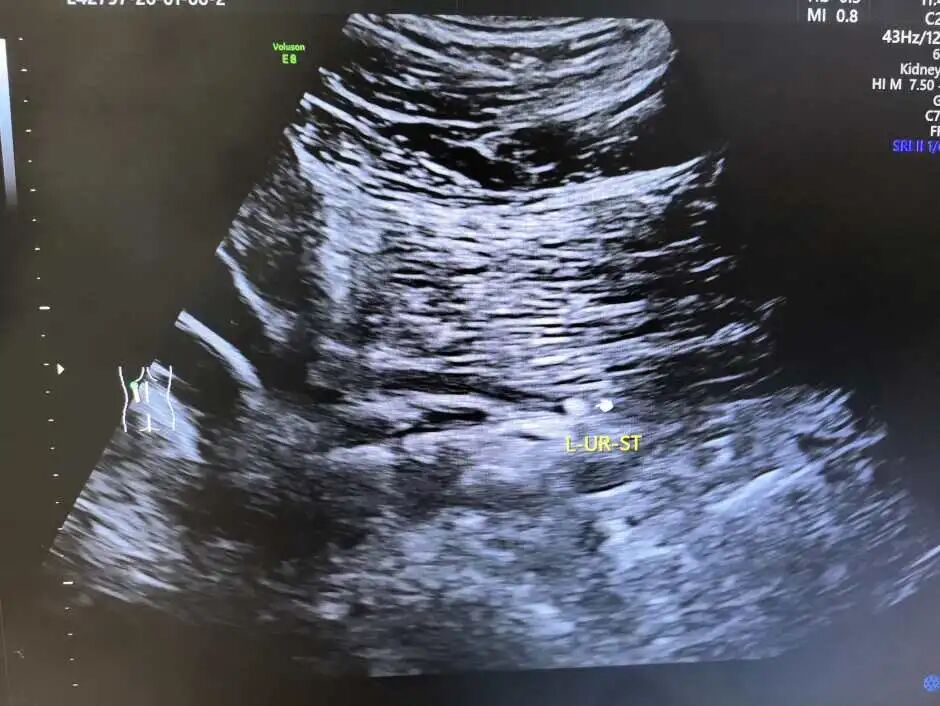

1.泌尿系结石:尤其对肾结石、输尿管及膀胱结石显示清晰,并能发现结石引起的肾积水。

左侧输尿管上段结石超声影像